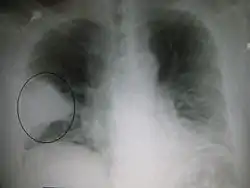

صورة بالأبيض والأسود تُظهر الأعضاء الداخلية في مقطع عرضي كما تظهرها الأشعة المقطعية. حيث يتوقع المرء أن يكون الأسود على الجانب الأيسر نشاهد منطقة أكثر بياضًا مع خطوط سوداء بداخلها.

كثيرًا ما يتم استخدام التصوير الشعاعي للصدر في التشخيص.[15] عند الأشخاص المصابين إصابة طفيفة، يُطلب التصوير فقط في الحالات التي من المرجح أن يحدث لديها مضاعفات أو التي لم تتحسن مع العلاج أو التي لم يتم التأكد من سبب إصابتها.[15][41] أما إذا كان الشخص مريضا بدرجة كافية تتطلب دخوله إلى المستشفى، فيُوصى بإجراء تصوير شعاعي للصدر.[41] علما أن النتائج لا ترتبط دومًا بخطورة المرض ولاتفرق تفريقا موثوقا به بين العدوى البكتيرية والعدوى الفيروسية.[15]

يمكن تصنيف ظواهر ذات الرئة التي تظهر في التصوير الشعاعي باعتبارها ذات الرئة الفصي وذات الرئة القصبي (والمعروف كذلك باسم ذات الرئة الفصيصي) وذات الرئة الخلالي.[44] يتصف المظهر الكلاسيكي لذات الرئة البكتيري المكتسب من المجتمع تصلد الرئة في فص رئوي قطعي واحد يعرف باسم ذات الرئة الفصي.[24] ولكن قد تختلف النتائج وتشيع أنماط أخرى في أنواع أخرى من ذات الرئة.[24] قد يظهر ذات الرئة الشفطي عتامات ثنائية الجانب في قاعدتي الرئتين وفي الجانب الأيمن.[24] وقد تظهر الصور الشعاعية لذات الرئة الفيروسي طبيعية أو مفرطة الانتفاخ أو بها مساحات مرقعة ثنائية الجانب أو تظهر مشابهة لذات الرئة البكتيري مع التكثف الفصي.[24] قد لا تكون هناك موجودات شعاعية في المراحل المبكرة من المرض، خاصةً في وجود الجفاف؛ أو ربما يصعب تفسيرها عند أولئك الذين يعانون من السمنة أو لديهم تاريخ مرض رئوي.[16] يمكن أن تُعطي الأشعة المقطعية معلومات إضافية في الحالات غير المحدّدة.[24]